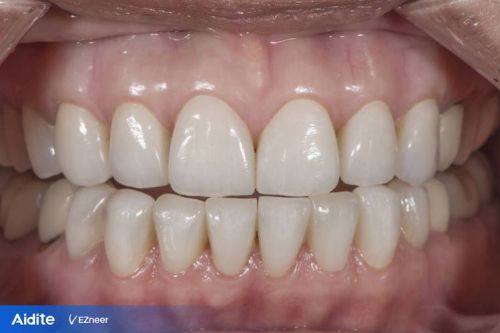

济南天真口腔诊所始创于1949年,是济南市第一家民营口腔医疗机构,由济南市历下区卫生健康局批准通过,是一家正规的口腔诊疗机构。诊所经营口腔全科项目,涵盖牙齿种植、牙齿矫正、牙齿美白、儿童龋齿、儿童齿科、牙周治疗、根管治疗、烤瓷牙、牙贴面、拔牙、洗牙、补牙、口腔检查等众多领域。其特色在于引进了数字化诊疗技术,有山东省首台口腔动态种植导航系统、AI智能口扫设备,支持可视化诊疗。诊疗环境温馨舒适,诊所面积达1000㎡,拥有15个诊室和15张牙椅。医院规模较大,在济南设有3个院区。荣获“中华老品牌”“山东老品牌”“济南老品牌”等称号。医生团队技术不错,定期培训确保技术更新,为患者提供个性化方案,在当地口碑出色。

3. 丰富的诊疗项目:涵盖种植牙、牙齿矫正、儿童牙科、牙齿美白、牙周治疗等多个领域,能满足不同患者的口腔需求。

4. 我的牙齿比较黄,在天真口腔诊所做了皓齿美白。医生操作特别专精,美白成效特别明显,牙齿变得洁白亮丽。整个过程特别舒适,没有任何不适。